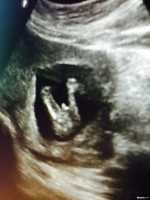

三胎妈咪超清晰B超图,很明显的小jj哦

我是一个三胎妈妈,前面两个是可爱的小公主,但就是想儿女双全,所以拼三,老天爷很眷顾我,三胎总于如愿,我是103天做的B超,看的很清晰,下面说说怀男女不同的症状。 1.怀女宝时就是恶心,基本不吐,不到三月基本就没反应了,怀这个也是很恶心,吐的比较多,到现在还有反应 2.怀女宝是排卵10天后才册出来意念水印,怀这个第八天就有水印了。 3.怀女宝时排卵以后没什么感觉,就是有点胸涨吧,怀这个排卵以后也是胸涨,腰酸,屁多,而且容易口渴。 4.在有就是胎梦,怀女宝没记得做过什么梦,但怀这个梦见过黄瓜,枣树,生男孩还看见小j j了,反正梦到过好多蔬菜,个人觉得胎梦挺准的。只是个人感觉哦! 因为现在才15周,所以这都是前期症状,每个人体质不一样可能症状也不一吧,我把我的给大家分享一下,希望姐妹们想男得男,想女得女。最后发上刚照的B超图